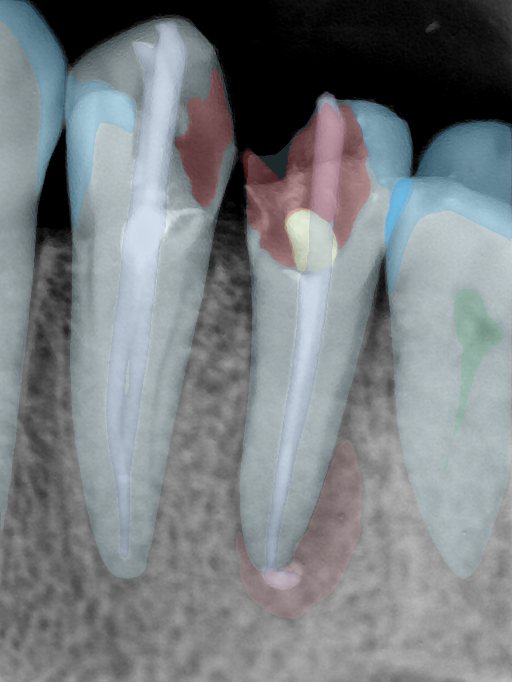

CR/DR 牙齿分割阶段记录

当前进展

- 完成了 CR/DR 牙齿相关分割训练

- 当前结果已经达到阶段预期,但仍有细节问题需要继续处理

相关测试

遇到的问题

- 训练过程中出现过 mask 下移问题

- 部分结果会出现 box 填充异常

- mask 边缘仍然有比较明显的锯齿感